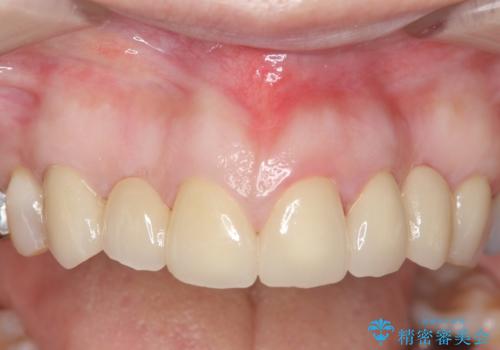

- 昔治療した前歯の被せ物の見た目を改善したいといらっしゃった方の症例です。

左上4番目の歯から右上3番目の歯まで計7歯のクラウンを除去し、オールセラミッククラウンによる補綴を行いました。

今回用いたオールセラミッククラウンはジルコニアフレームという白い素材の上にセラミックを盛っているため、審美性が非常に高いのが特徴です。

また、ジルコニアは人工ダイヤモンドの材料にも使われているほど高い強度を持っており、そのためオールセラミッククラウンは審美性だけでなく、奥歯やブリッジの補綴も可能とするクラウンです。